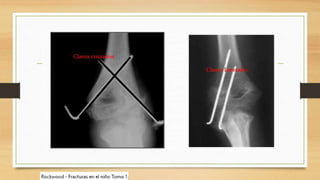

AGUJA KIRHSNER

TECNICAS DE REDUCCION

FRACTURAS CONDILEAS

• PRINCION DE TORNILLO INTERFRAGMENTARIO